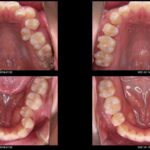

実際のインビザライン装着時の、口の中の写真です。

透明なマウスピースでできている為、ほとんど目立ちません。今回は、上の歯だけ矯正を予定しました。

アタッチメントを装着しました。「マウスピースの維持」と「歯に加わる力をコントロール」するのに役立ちます。